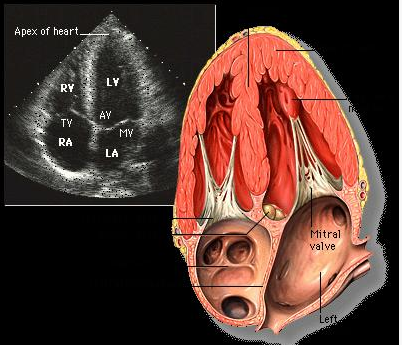

(图) 心底短轴切面 (二维超声心动图)

图片尺寸944x727

经典心脏超声切面图及解剖解释

图片尺寸893x584